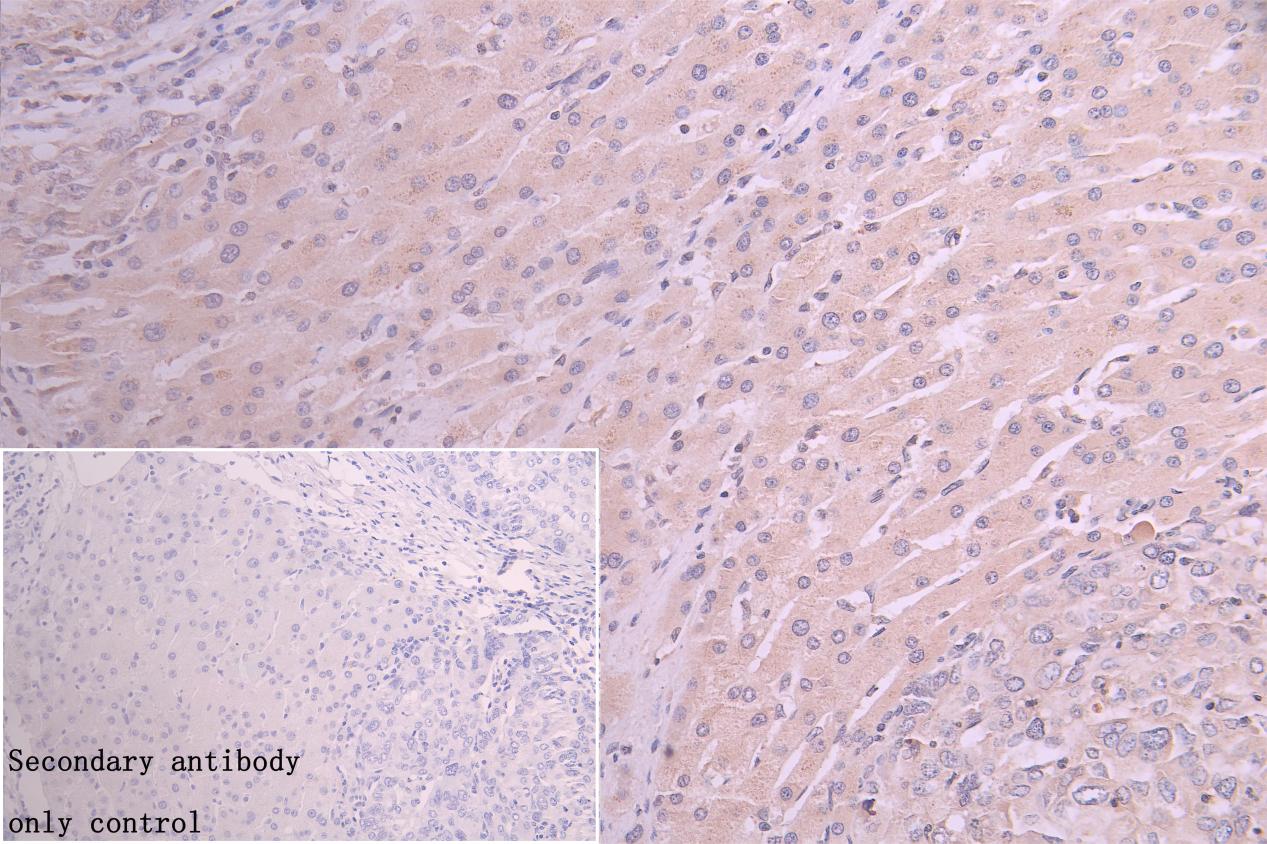

IHC image of CSB-PA891974DSR2HU diluted at 1:150 and staining in paraffin-embedded human liver cancer performed on a Leica BondTM system. After dewaxing and hydration, antigen retrieval was mediated by high pressure in a citrate buffer (pH 6.0). Section was blocked with 10% normal goat serum 30min at RT. Then primary antibody (1% BSA) was incubated at 4°C overnight. The primary is detected by a Goat anti-rabbit polymer IgG labeled by HRP and visualized using 0.05% DAB. Secondary antibody only control: uses 1% BSA instead of primary antibody

IHC image of CSB-PA891974DSR2HU diluted at 1:150 and staining in paraffin-embedded human prostatecancer performed on a Leica BondTM system. After dewaxing and hydration, antigen retrieval was mediated by high pressure in a citrate buffer (pH 6.0). Section was blocked with 10% normal goat serum 30min at RT. Then primary antibody (1% BSA) was incubated at 4°C overnight. The primary is detected by a Goat anti-rabbit polymer IgG labeled by HRP and visualized using 0.05% DAB. Secondary antibody only control: uses 1% BSA instead of primary antibody